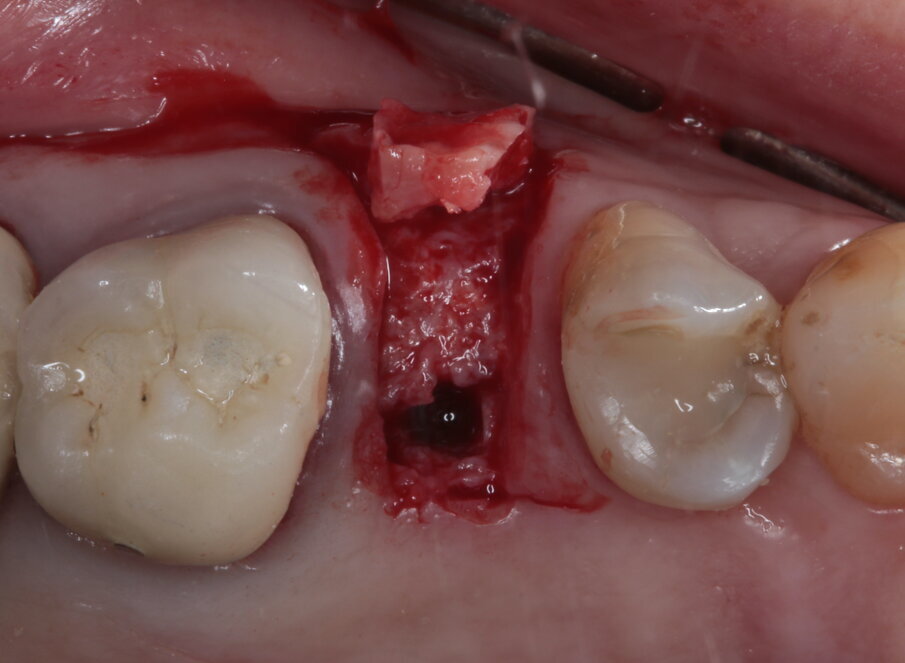

Il piano di trattamento prevede quindi l’estrazione del 25 giudicato non mantenibile, la preservazione dell’alveolo post estrattivo, l’inserimento differito di un impianto e il suo carico una volta terminato il processo di osteointegrazione. Per quanto riguarda l’elemento 24, si programma la terapia endodontica e la successiva ricostruzione diretta. Viene effettuata un’estrazione atraumatica del 25, la rimozione del tessuto infiammatorio periapicale e il posizionamento di un sostituto osseo addizionato con acido ialuronico reticolato ad alto peso molecolare (HyaDENT BG) al fine di ottenere una più rapida stabilizzazione del coagulo ed una buona stabilità dell’innesto, determinanti per il mantenimento del volume ottimale. Questo viene poi coperto con una membrana di collagene suino imbustata al di sotto dei tessuti vestibolari e palatali (Figg. 6-10).